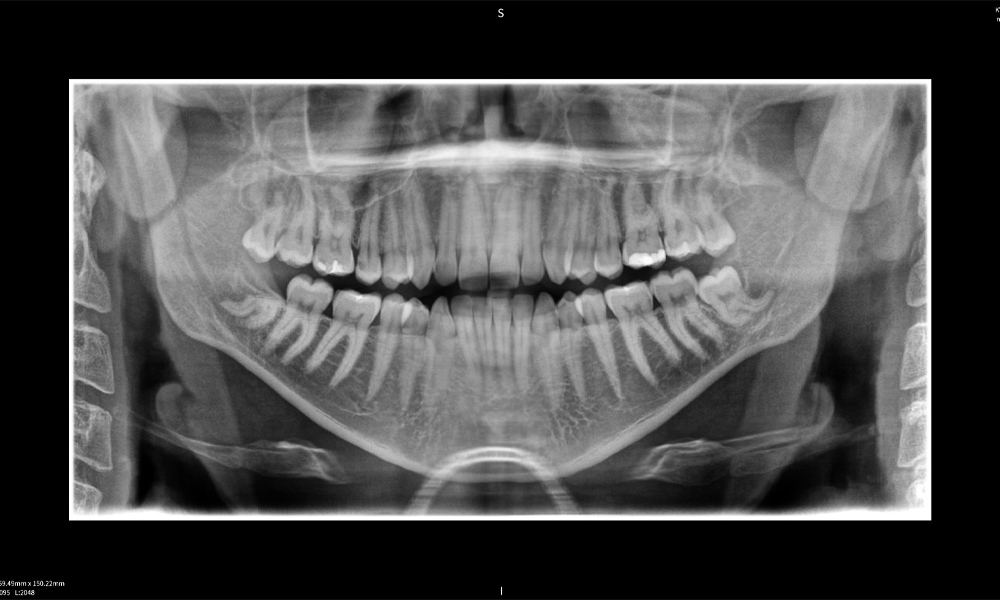

Nachstehend finden Sie einen Fall von Dr. med. dent. Oliver A. Centrella, in dem die CBCT-Aufnahmen mit Seethrough Max entscheidende Informationen zur komplexen Anatomie sowie zur kritischen Beziehung zwischen den Weisheitszähnen und dem Nervus alveolaris inferior lieferten. Bei diesem Fall besteht eine Indikation zur chirurgischen Entfernung der Weisheitszähne.

Abbildung a: Bildgebungsergebnisse von Seethrough Max vor einem schwarzen Hintergrund.

Abbildung a

Abbildung e: Panoramaröntgenaufnahme dient der initialen Beurteilung und zeigt die allgemeine Zahnstellung sowie mögliche pathologische Veränderungen auf. Insbesondere ist auf der rechten Seite (Zahn 48) die Situation nach einer Kronenamputation durch einen externen Behandler ersichtlich. Die beiden stark gekrümmten Wurzeln verbleiben in enger topographischer Beziehung zum Nervus alveolaris inferior im Knochen. Dies deutet auf eine bewusste Entscheidung zur Vermeidung eines erhöhten Risikos einer Nervenläsion während einer vollständigen Extraktion hin und stellt einen klinisch relevanten Befund dar. Zusammenfassend liefern die CBCT-Aufnahmen mit Seethrough Max entscheidende Informationen über die komplexe Anatomie und die kritische Beziehung zwischen den Weisheitszähnen und dem Nervus alveolaris inferior. Diese detaillierte präoperative Diagnostik ist unerlässlich für die sichere und erfolgreiche Durchführung chirurgischer Eingriffe im Unterkieferbereich.